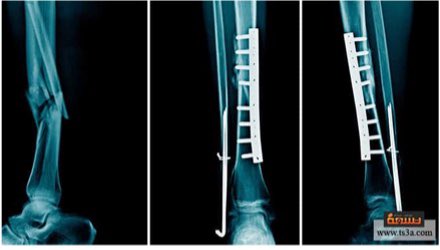

🔹 الخيارات الجراحية:

- تركيب مسمار النخاع (Intramedullary nail): يتم إدخال قضيب معدني مصمم خصيصًا في قناة الساق و يمر القضيب عبر الكسر لإبقائه في موضعه مما يساعد على التئام الساق.

- التثبيت الداخلي بالشرائح و المسامير.

- التثبيت الخارجي (External fixation): عبارة عن إطار خارج الساق يتم تثبيته في العظام بدبابيس، يوفر هذا الجهاز الثبات للعظام خلال فترة الالتئام و تتم إزالته عادة بعد التئام الكسر.